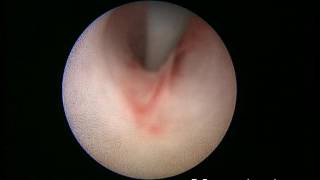

TURis Plasma Vaporization εξάχνωση προστάτη Δρ. Κυμηνάς Laser λιθοθρυψία με εύκαμπτο ουρηρτηροσκόπιο Εξελκυσμός λίθου ουρητήρα Διουρηθρική όγκου ουροδόχου κύστεως 1 www.kyminas-urology.gr Διουρηθρική προστατεκτομή TURis Δρ. Κυμηνάς Ευάγγελος www.kyminas-urology.gr TUR-P Διουρηθρική προστατεκτομή TURis 1 Δρ. Κυμηνάς Ευάγγελος www.kyminas-urology.gr Laser λιθοθρυψία λίθου ουρητήρα Δρ. Κυμηνάς Ευάγγελος www.kyminas-urology.gr ουρητηροσκόπηση καρκίνος ουρητήρα Δρ. Κυμηνάς Ευάγγελος www.kyminas-urology.gr Ουρητηροκήλη Δρ. Κυμηνάς Ευάγγελος www.kyminas-urology.gr Διουρηθρική θηλώματος κύστεως υψηλού βαθμού κακοήθειας Kyminas-urology.gr